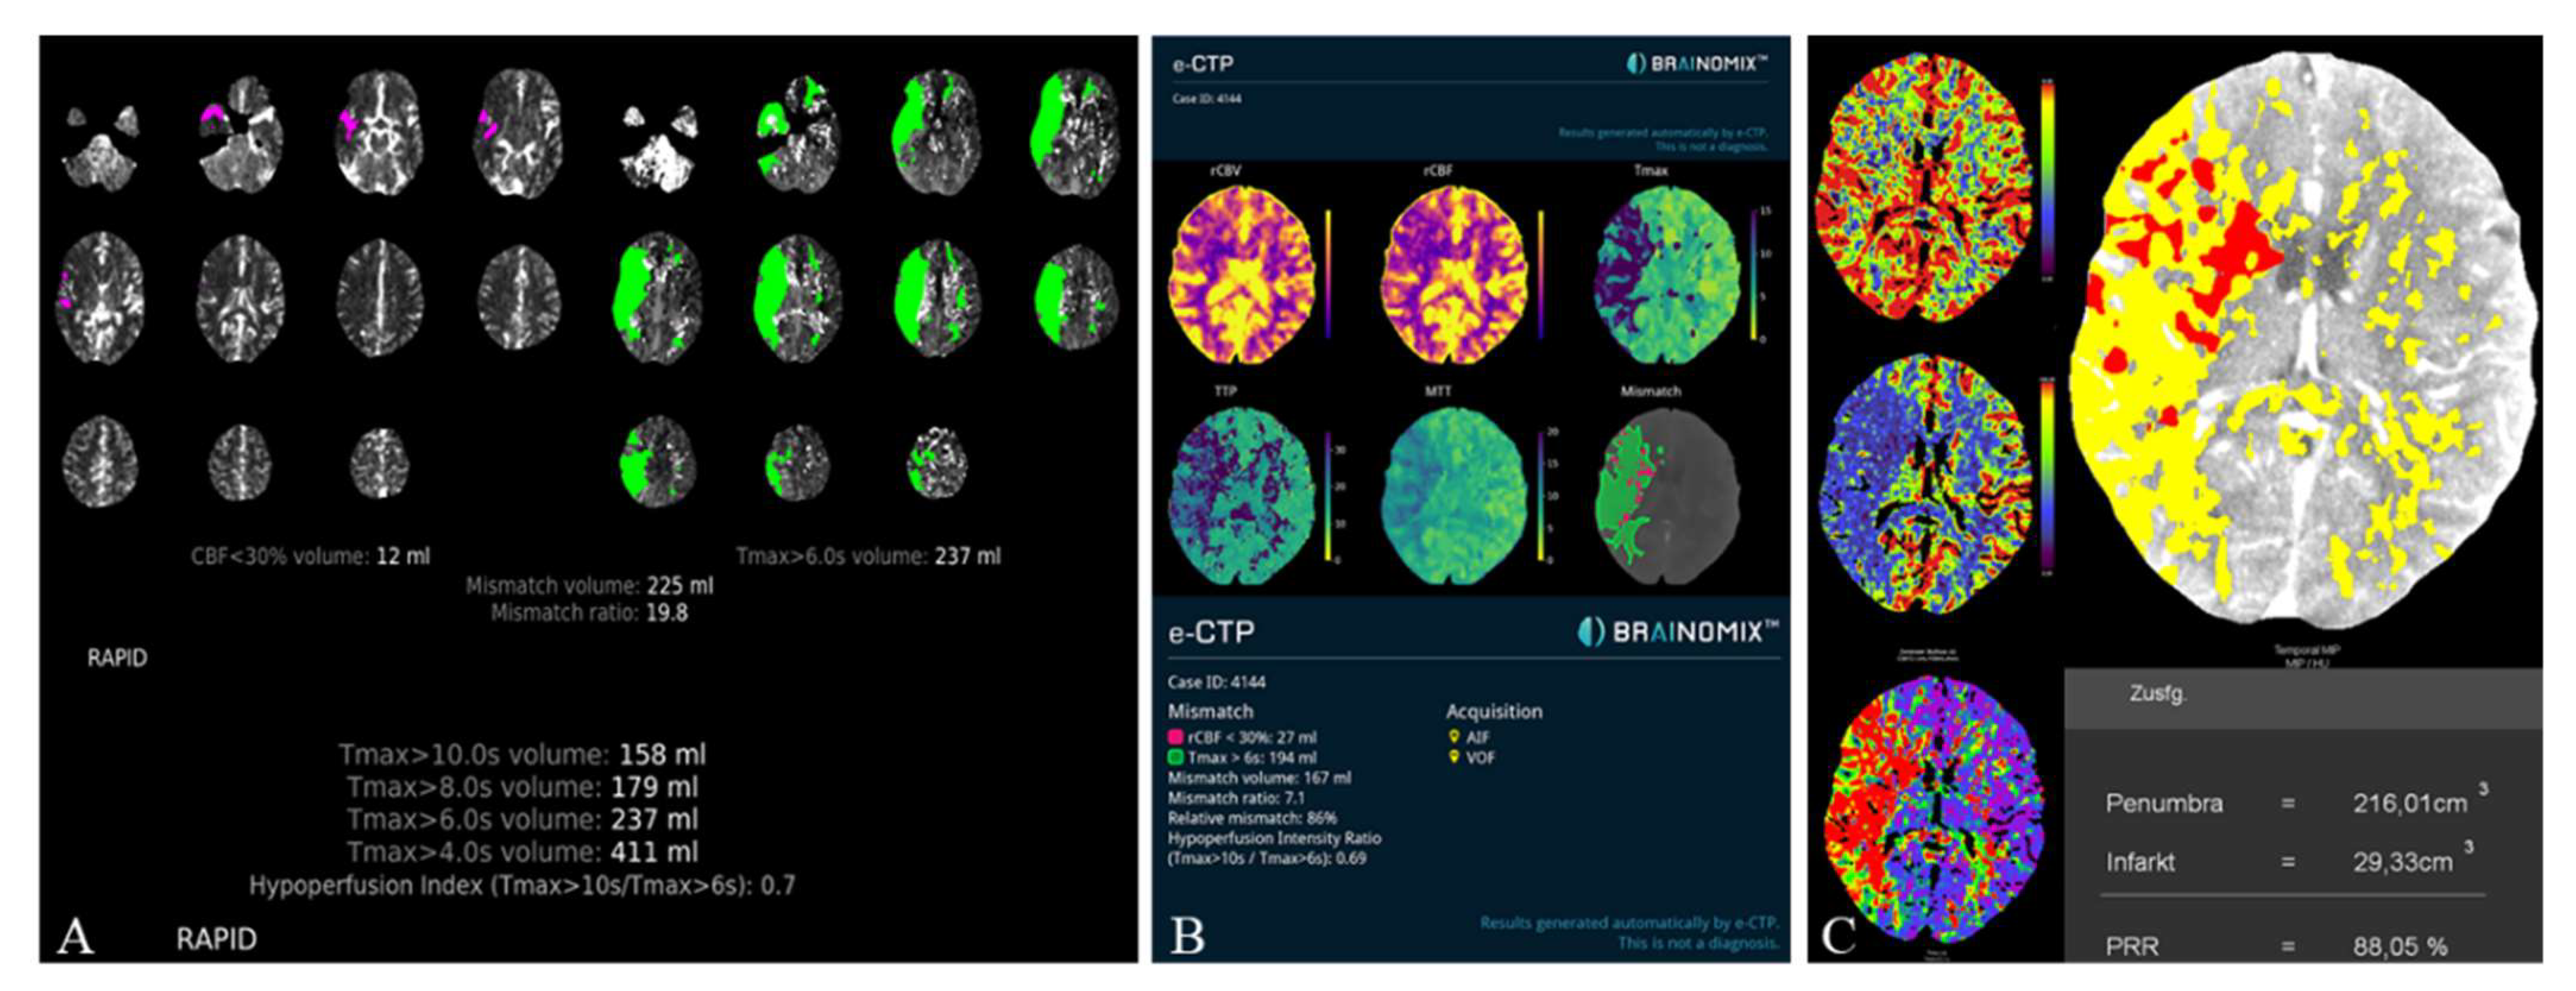

The HVs differed significantly between RAPID and Syngo (−21.7 ± 37.9 mL, p < 0.001) as well as Brainomix and Syngo (−28.9 ± 45.1 mL, p < 0.001), while there were no significant differences between RAPID and Brainomix (−8.3 ± 41.0 mL, p = 0.22). The same could be observed for the mismatch volumes, which did not show significant differences between RAPID and Brainomix (3.8 ± 43.5 mL, p = 0.29), but between Brainomix and Syngo (−27.7 ± 46.3 mL, p < 0.001) as well as RAPID and Syngo (−25.3 ± 41.4 mL, p < 0.001). However, correlation of the mismatch volumes was high among all software packages (r > 0.8, p < 0.001). All software packages showed small differences (between 0.9 and 3.1 mL) in the indicated ischemic core volumes (ICV) without significant differences (p > 0.3). Median HIR was 0.6 (0.4–0.7) for all software applications. Figure 3 shows the automatically generated perfusion results by packages A, B, and C of a patient with M1-occlusion of the right hemisphere. The FIV on follow-up CT 24 h after futile recanalization is shown on Figure 4.

Figure 3. Illustrative Perfusion results of a patient with M1-occlusion of the right hemisphere (RAPID (A), Brainomix (B), and Syngo (C)). Packages A and B provide automated calculation of the HIR, which can be directly read from the perfusion maps. For Syngo, the HIR was calculated with a result of 0.7.